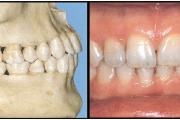

Vali sind huvitav pilt ja me näitame sellega seotud haigust ja sümptomeid